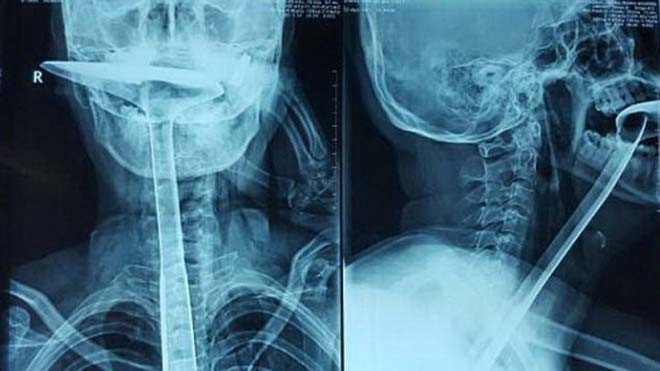

Hình ảnh X-quang cho thấy bàn xẻng dài trong thực quản bệnh nhân. Ảnh: Imaginechina/Rex Shutterstock.

Đầu tiên, cô thử với các ngón tay, sau đó là 3 chiếc đũa, cả ba đều bị gãy. Guan quyết định dùng vật lớn hơn và cho xẻng nấu ăn bằng bạc dài tới 30 cm vào miệng, rồi chọc dần xuống cổ họng.

Sau ca phẫu thuật cấp cứu, các bác sĩ đã lấy bàn xẻng to và cứng ra khỏi cổ họng, bảo toàn mạng sống cho bệnh nhân. Tuy nhiên, họ buộc phải cắt đi đoạn thực quản dài 20 cm đã bị tổn thương, không thể phục hồi. Các bác sĩ kéo dạ dày nối thông lên thực quản thay cho đoạn vừa bị cắt bỏ.